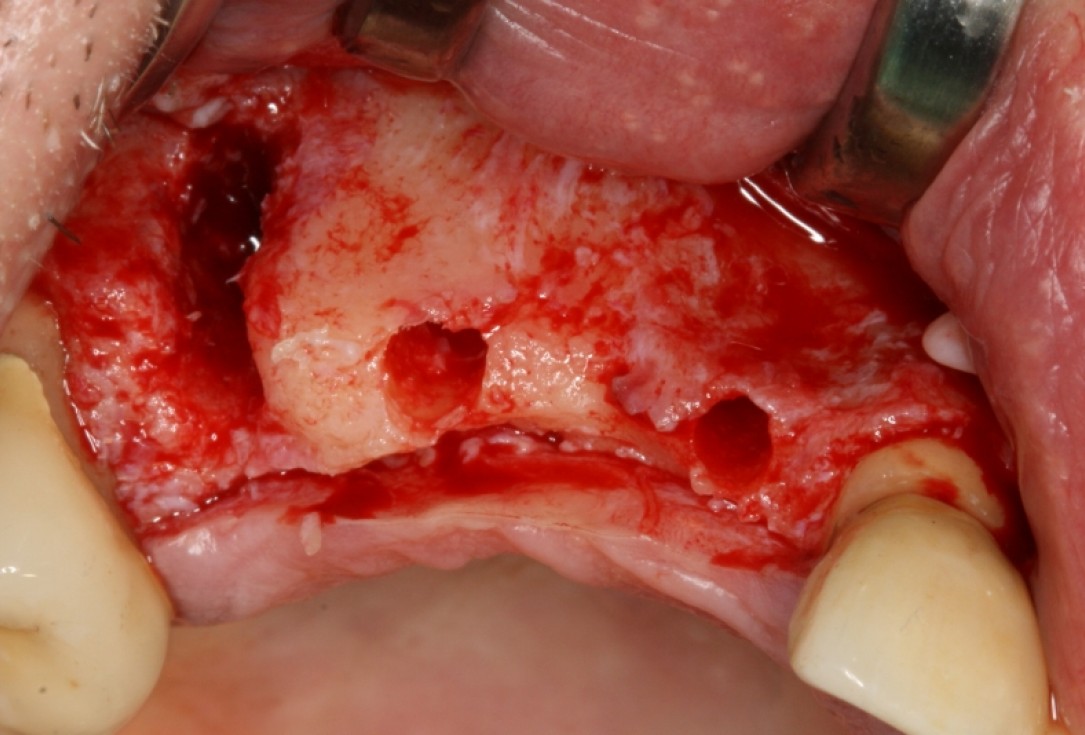

Three implants placed in a narrow posterior mandible